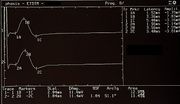

| 17:31, 26 February 2023 | Bruxer SP1.jpeg (file) |  |

141 KB | 1 | |